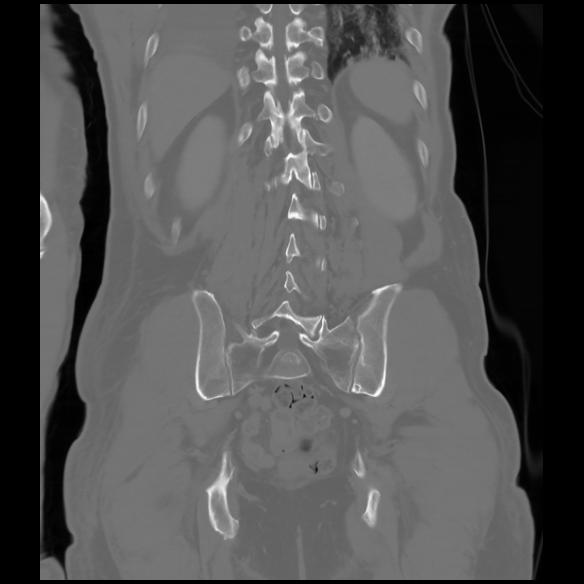

6 CUERPO,CE,Coronal,3.000,CUERPO,Coronal,